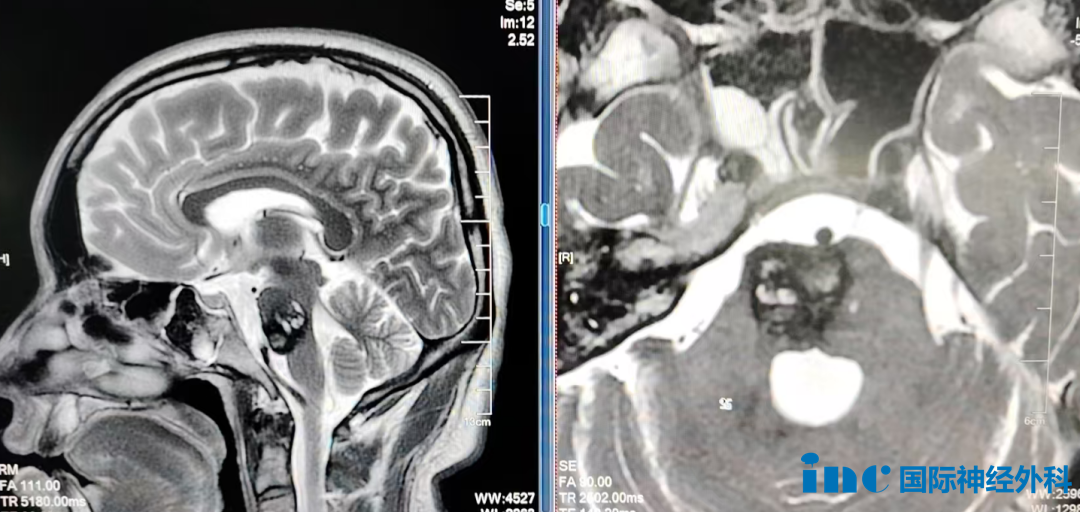

根据术前磁共振成像检查,50岁的方女士在过去六年期间,已经接受了多次开颅手术以及多次经鼻内镜手术,部分手术在美国多家知名医疗机构完成。由于手术次数较多,患者本人甚至难以记清具体次数,肿瘤病理分级也从最初的Ⅰ级进展为Ⅱ级。

肿瘤体积巨大,对垂体及垂体柄形成明显挤压,并且包绕了周围重要的血管与神经结构,这些结构包括颈内动脉、展神经、视神经以及动眼神经。肿瘤周边的血管壁异常脆弱,轻微触碰即存在破裂出血的风险。对于巴特朗菲教授这位国际神经外科权威专家来说,处理此类棘手情况已是临床常态。

最终肿瘤切除效果令人满意,可以清晰观察到解剖结构,垂体柄与垂体均得到完好保留,术前备用的血袋在术中并未使用。巴特朗菲教授在术后表示:“结果不能再好,整个过程如预期般顺利。”